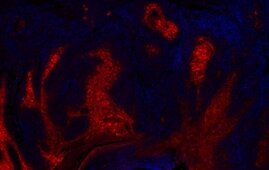

Wie kann man magnetische Bakterien zur Bekämpfung von Krebsgeschwüren nutzen, dies wollen Forschende der ETH Zürich herausfinden. Sie haben nun einen…